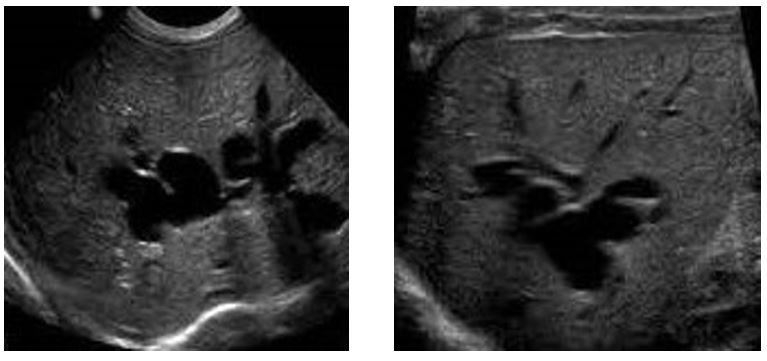

what is this disease associated with…this is carolis disease

MEDULLARY SPONGE KIDNEY

Caroli’s Disease (medullary sponge kidney) is strongly associated